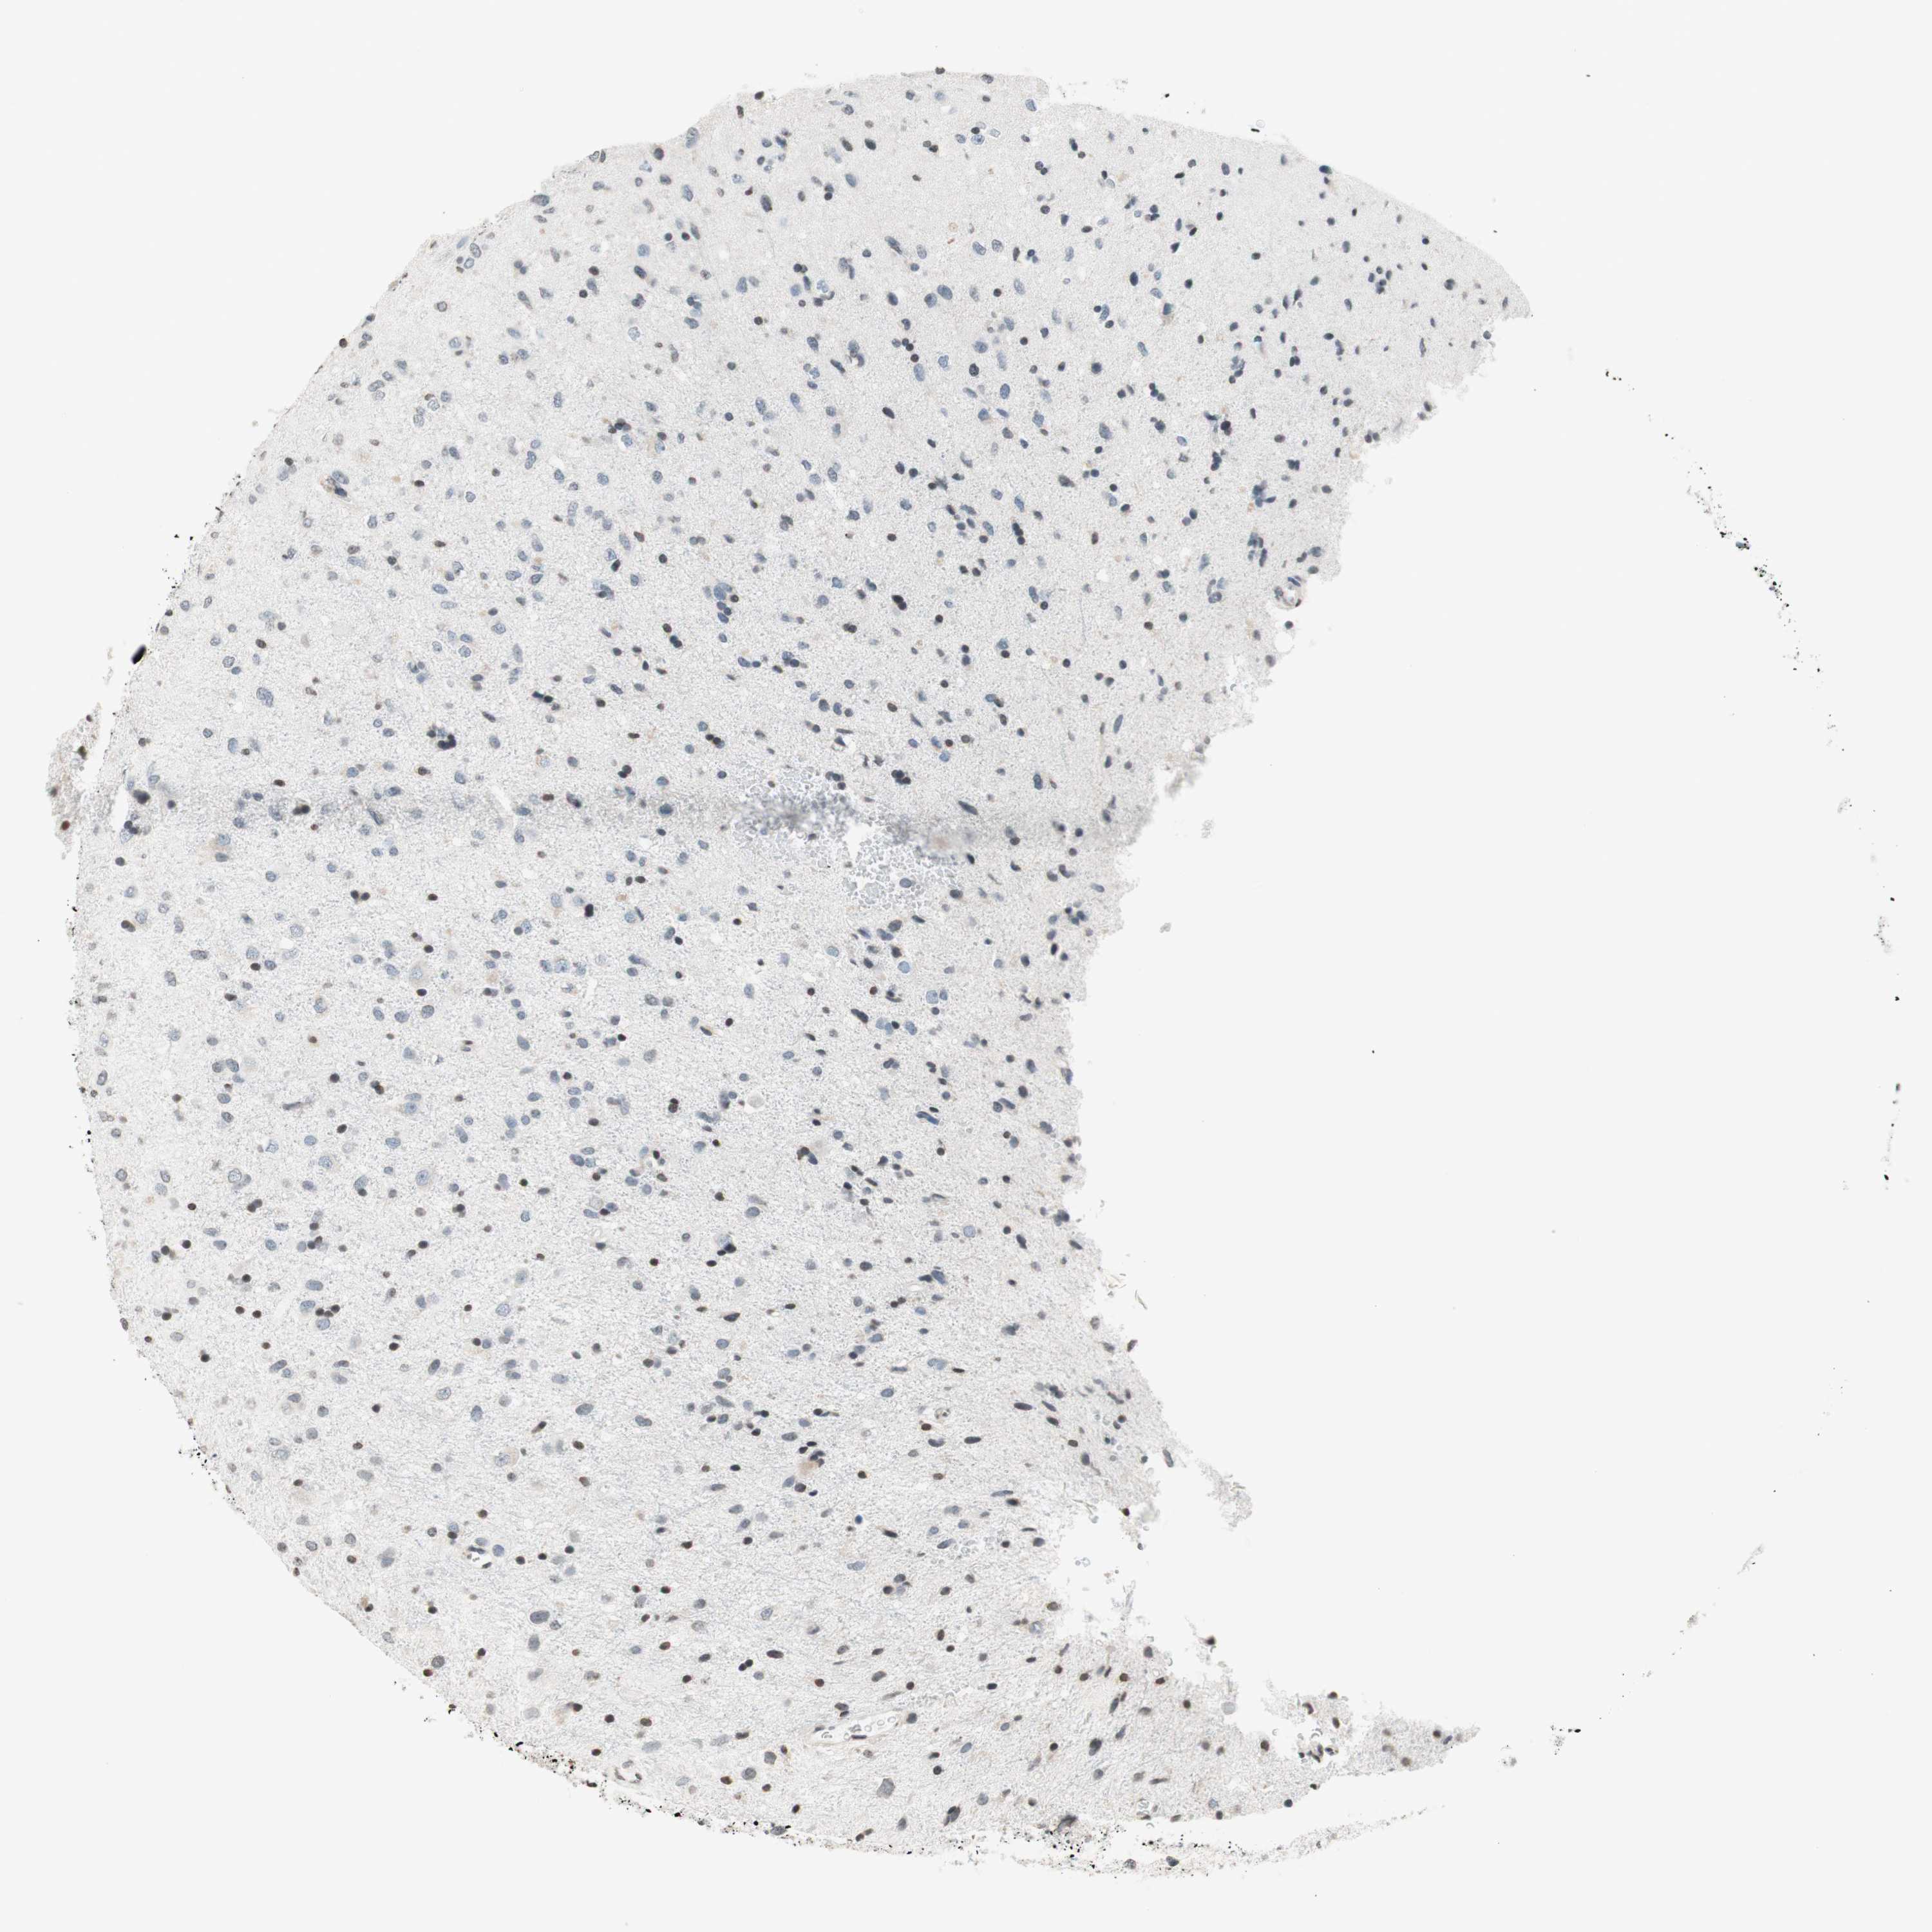

GLIOMA - Protein expressioni

A mouse-over function shows sample information and annotation data. Click on an image to view it in a full screen mode. Samples can be filtered based on level of antibody staining by selecting one or several of the following categories: high, medium, low and not detected. The assay and annotation is described here.

Note that samples used for immunohistochemistry by the Human Protein Atlas do not correspond to samples in the TCGA dataset.

Antibody stainingi

Antibody staining in the annotated cell types in the current human tissue is reported as not detected, low, medium, or high, based on conventional immunohistochemistry profiling in selected tissues. This score is based on the combination of the staining intensity and fraction of stained cells.

Each image is clickable and will lead to virtual microscopy that enables deeper exploration of all samples and also displays staining intensity scores, fraction scores and subcellular localization as well as patient and tissue information for each sample.

Antibody HPA003739

Antibody CAB009737

Staining

High

Medium

Low

Not detected

Intensity

Strong

Moderate

Weak

Negative

Quantity

>75%

75%-25%

<25%

None

Location

Nuclear

Cytoplasmic/membranous

Cytoplasmic/membranous,nuclear

Glioma, malignant, High grade

Glioma, malignant, Low grade

Glioma, malignant, NOS